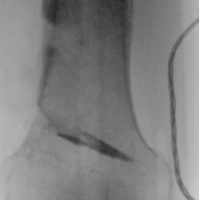

At 8 weeks postoperatively, the patient was pain-free, with a range of motion of 0–100° flexion, 30° abduction, 30° adduction, 30° internal rotation, and 30° external rotation. She had successfully resumed mobility, taking several steps with the assistance of a wheeled walker. At the 6-month follow-up, the patient reported walking and moving as she did before the trauma and surgery. Radiographic evaluation at that time confirmed implant stability and showed signs of bony consolidation of the greater trochanter (Figs. 3 and 4).

Figure 4: Six months post-operative axial hip X-ray.